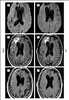

Gyriform cortical/subcortical T2 hypointensity

May Be Caused by

Acute cortical infarction

Acute subarachnoid hemorrhage

Meningitis

Subacute cortical infarction

Superficial siderosis